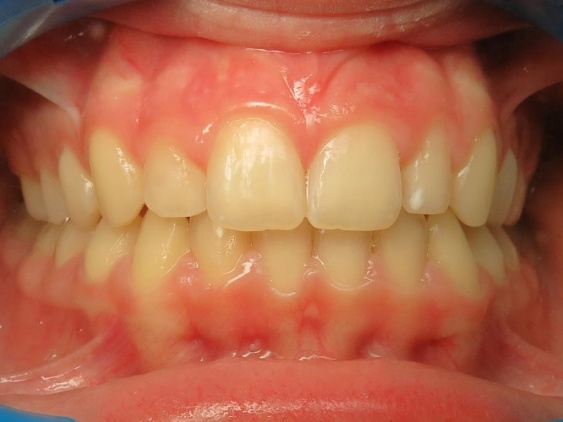

4 - Évolution du visage avant et après traitement.

Le profil est clairement amélioré. Ce traitement est une réussite à la fois fonctionnelle, en rétablissant une occlusion stable, et esthétique, avec un menton bien projeté. L’analyse céphalométrique de Delaire avait anticipé cette croissance favorable, confirmée par le résultat final conforme au diagnostic initial.